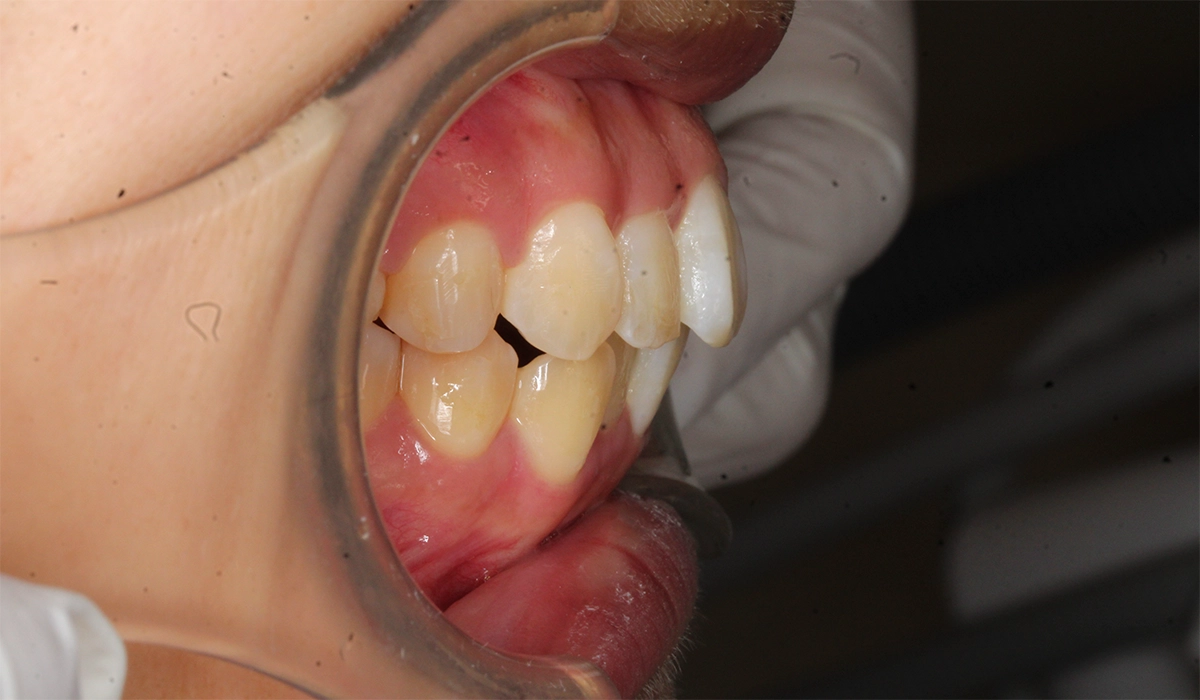

術前:右側

今回ご紹介する患者様は、上顎前歯の突出、全体的な歯並びのがたつきを気にされており、矯正検査後叢生2級と診断いたしました。

| 主訴 | 上顎前歯の突出、全体的な歯並びのがたつきが気になる |

| 治療期間 | 22カ月 |

| 治療費用 | 990,000円(税込) |

| 治療内容 | 上顎前歯の突出、全体的な歯並びのがたつきを気にされており、矯正検査後叢生2級と診断いたしました。 |